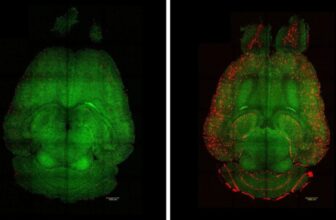

Scientists on Tuesday reported that that they had reversed Alzheimer’s disease in mice, a feat that provides hope of a possible remedy for the devastating type of dementia in people. In a ...